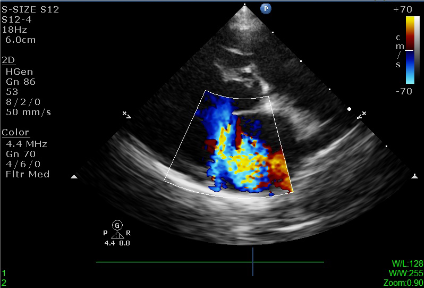

目前治療仍大多採內科持續服用藥物方式延緩病情發展,並定期回診藉由聽診,量測血壓,追蹤腎指數,胸腔X光以及心臟超音波來監控病情已獲得良好生活品質。

經由心臟超音波,胸腔X光,血壓,及血液檢查完整評估病犬心臟病分級。並依照其心臟病分期,給予所需的藥物及治療。